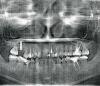

StomDoc Опубликовано 10 марта, 2013 Поделиться Опубликовано 10 марта, 2013 Был открытый синус с увеличением ширины на 5 сутки прорезались швы из за недостаточной мобилизации лоскута наверное. Можно ли как то улучшить ситуацию мягкими тканями???P.S.Прошу прощения за качество снимка((( Ссылка на комментарий

StomDoc Опубликовано 11 марта, 2013 Автор Поделиться Опубликовано 11 марта, 2013 Там сначала раздвинули а потом пригласили хирурга и сказали ставь как есть!!! Я бы вообще не заморачивался с имплантацией тут так как очень маленькие корни и после раздвижения подвижность сильная!!! Торк маленький был это фото спустя 10 дней сейчас прошло 4 месяца картина примерно такая же!!!! Так чтотсоветует просто поставить и не усложнять???? Ссылка на комментарий

StomDoc Опубликовано 11 марта, 2013 Автор Поделиться Опубликовано 11 марта, 2013 Ну вот как то так было!!!Куда с такими корнями ортодонтия??? Ссылка на комментарий